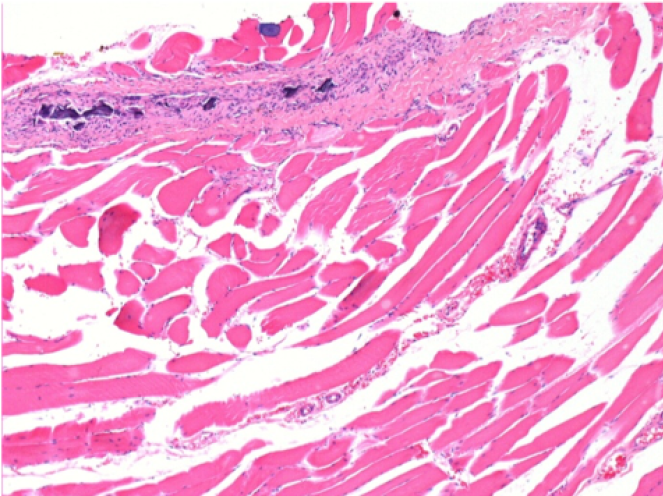

1 month after Endopeel Injection 0.1ml in the right pretibial muscle.

What is seen in black on the pictures is not a necrosis like could imagine some scientifics !

In fact, 4 conclusions have to be taken in consideration